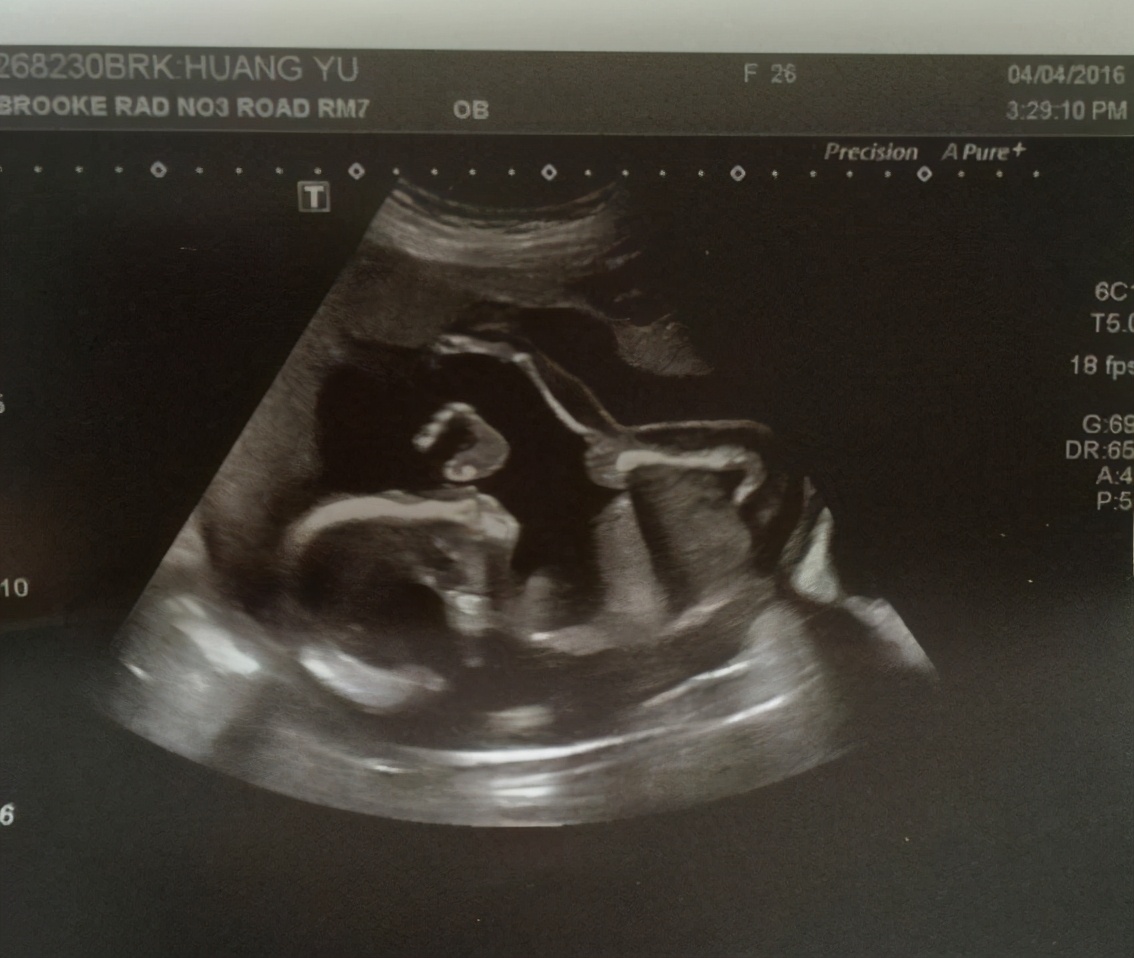

璇璇怀孕的时候,宝宝特别“活泼”,她明明是初孕妇,但胎动却比很多经孕妇还早。

产检的时候,宝宝也是特别活泼的乱动,医生笑着说:“宝宝是个小机灵鬼啊,这是害怕探头,往回躲呢。”

孕妈连忙着急地问医生,宝宝是不是有什么问题。产检的大夫告诉璇璇,胎儿对外界非常敏感,这是大脑发育的好的表现,一看宝宝就是个聪明娃。